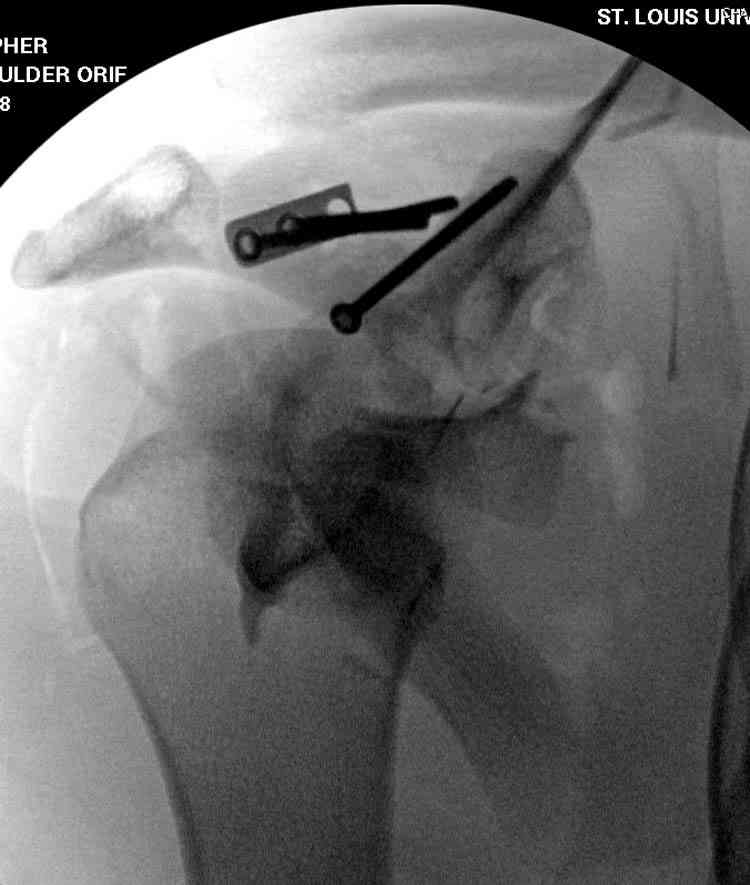

На снимке (№6 компьютерная томограмма и 3D №7) перелом клювовидного отростка.

Передним дельтопекторальным Bankart доступом намного легче провести фиксация отростка, но тогда репозиция и фиксация колонн затрудняется, поэтому был применен стандартный Judet задний доступ.

Двумя шурупами сзади на пластине (вместе шайбы)

провели удержание репозиции, а фиксацию провели

следующим косым шурупом.

Последующие этапы на снимках.